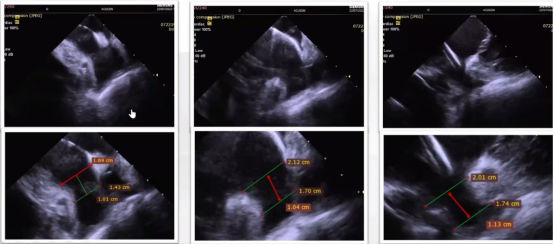

常规三个角度评估:首先从RA中部顺逆时针旋转,观察左心房短轴,判断是否存在血栓;然后从RA中部复合弯看左心房长轴;最后从RVOT低位顺逆时针旋转,观察左心耳是否存在血栓。需要注意的是,初次使用者不建议进入到肺动脉。在右室流出道主动脉短轴扇面调整方向,可以看到左心耳的远端结构。

ICE导管分别在左上肺静脉、左房中部及二尖瓣瓣环位置评估左心耳,并且测量锚定区和心耳开口。

ICE导管在二尖瓣瓣环位置(135°),硬币法展开,固定盘卡在上叶中,位置合适。